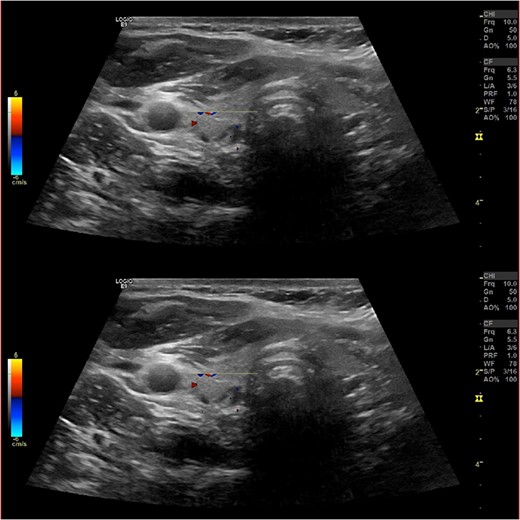

Ultrasound of the neck (Fig. 1), CT and parathyroid sestamibi scan (Fig. 2) failed to localize parathyroid, and all studies showed normal thyroid with no other neck masses or suspicious lymph nodes. Magnetic resonance imaging neck showed no evidence of parathyroid adenoma in the expected typical gland locations or ectopic cervical or upper mediastinum. Therefore, we requested a fluorocholine (FCH) positron emission tomography (PET)/CT (Figs 3 and 4) for localization, which showed normal physiological uptake of the choline in the neck. There was no abnormal focal choline lesion in the thyroid gland or the visualized organs (unremarkable visualized part of the lungs). So, the result was a negative choline scan.

Ultrasound neck showing normal thyroid gland and no abnormal parathyroid.